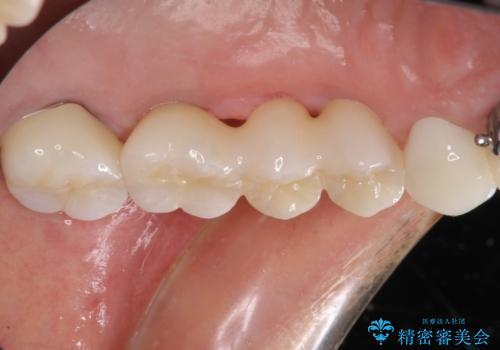

ブリッジの土台が割れて痛い インプラントによる補綴治療

- 上の奥歯に装着されているブリッジが痛むとのことで来院された患者様です。

診察した結果、ブリッジの土台となっている歯が割れていたため、抜歯が必要となりました。

欠損している歯数が多いため、ブリッジによる補綴治療は困難と判断し、インプラントによる補綴治療を行うこととしました。

インプラントを埋入するために必要な骨の高さがなかったため、上顎洞底の粘膜を挙上しました。

手術後は処置部に痣や腫脹が出現したり、痛みが出たりしましたが、補綴治療後は咬み合わせが安定し、大変満足していただきました。